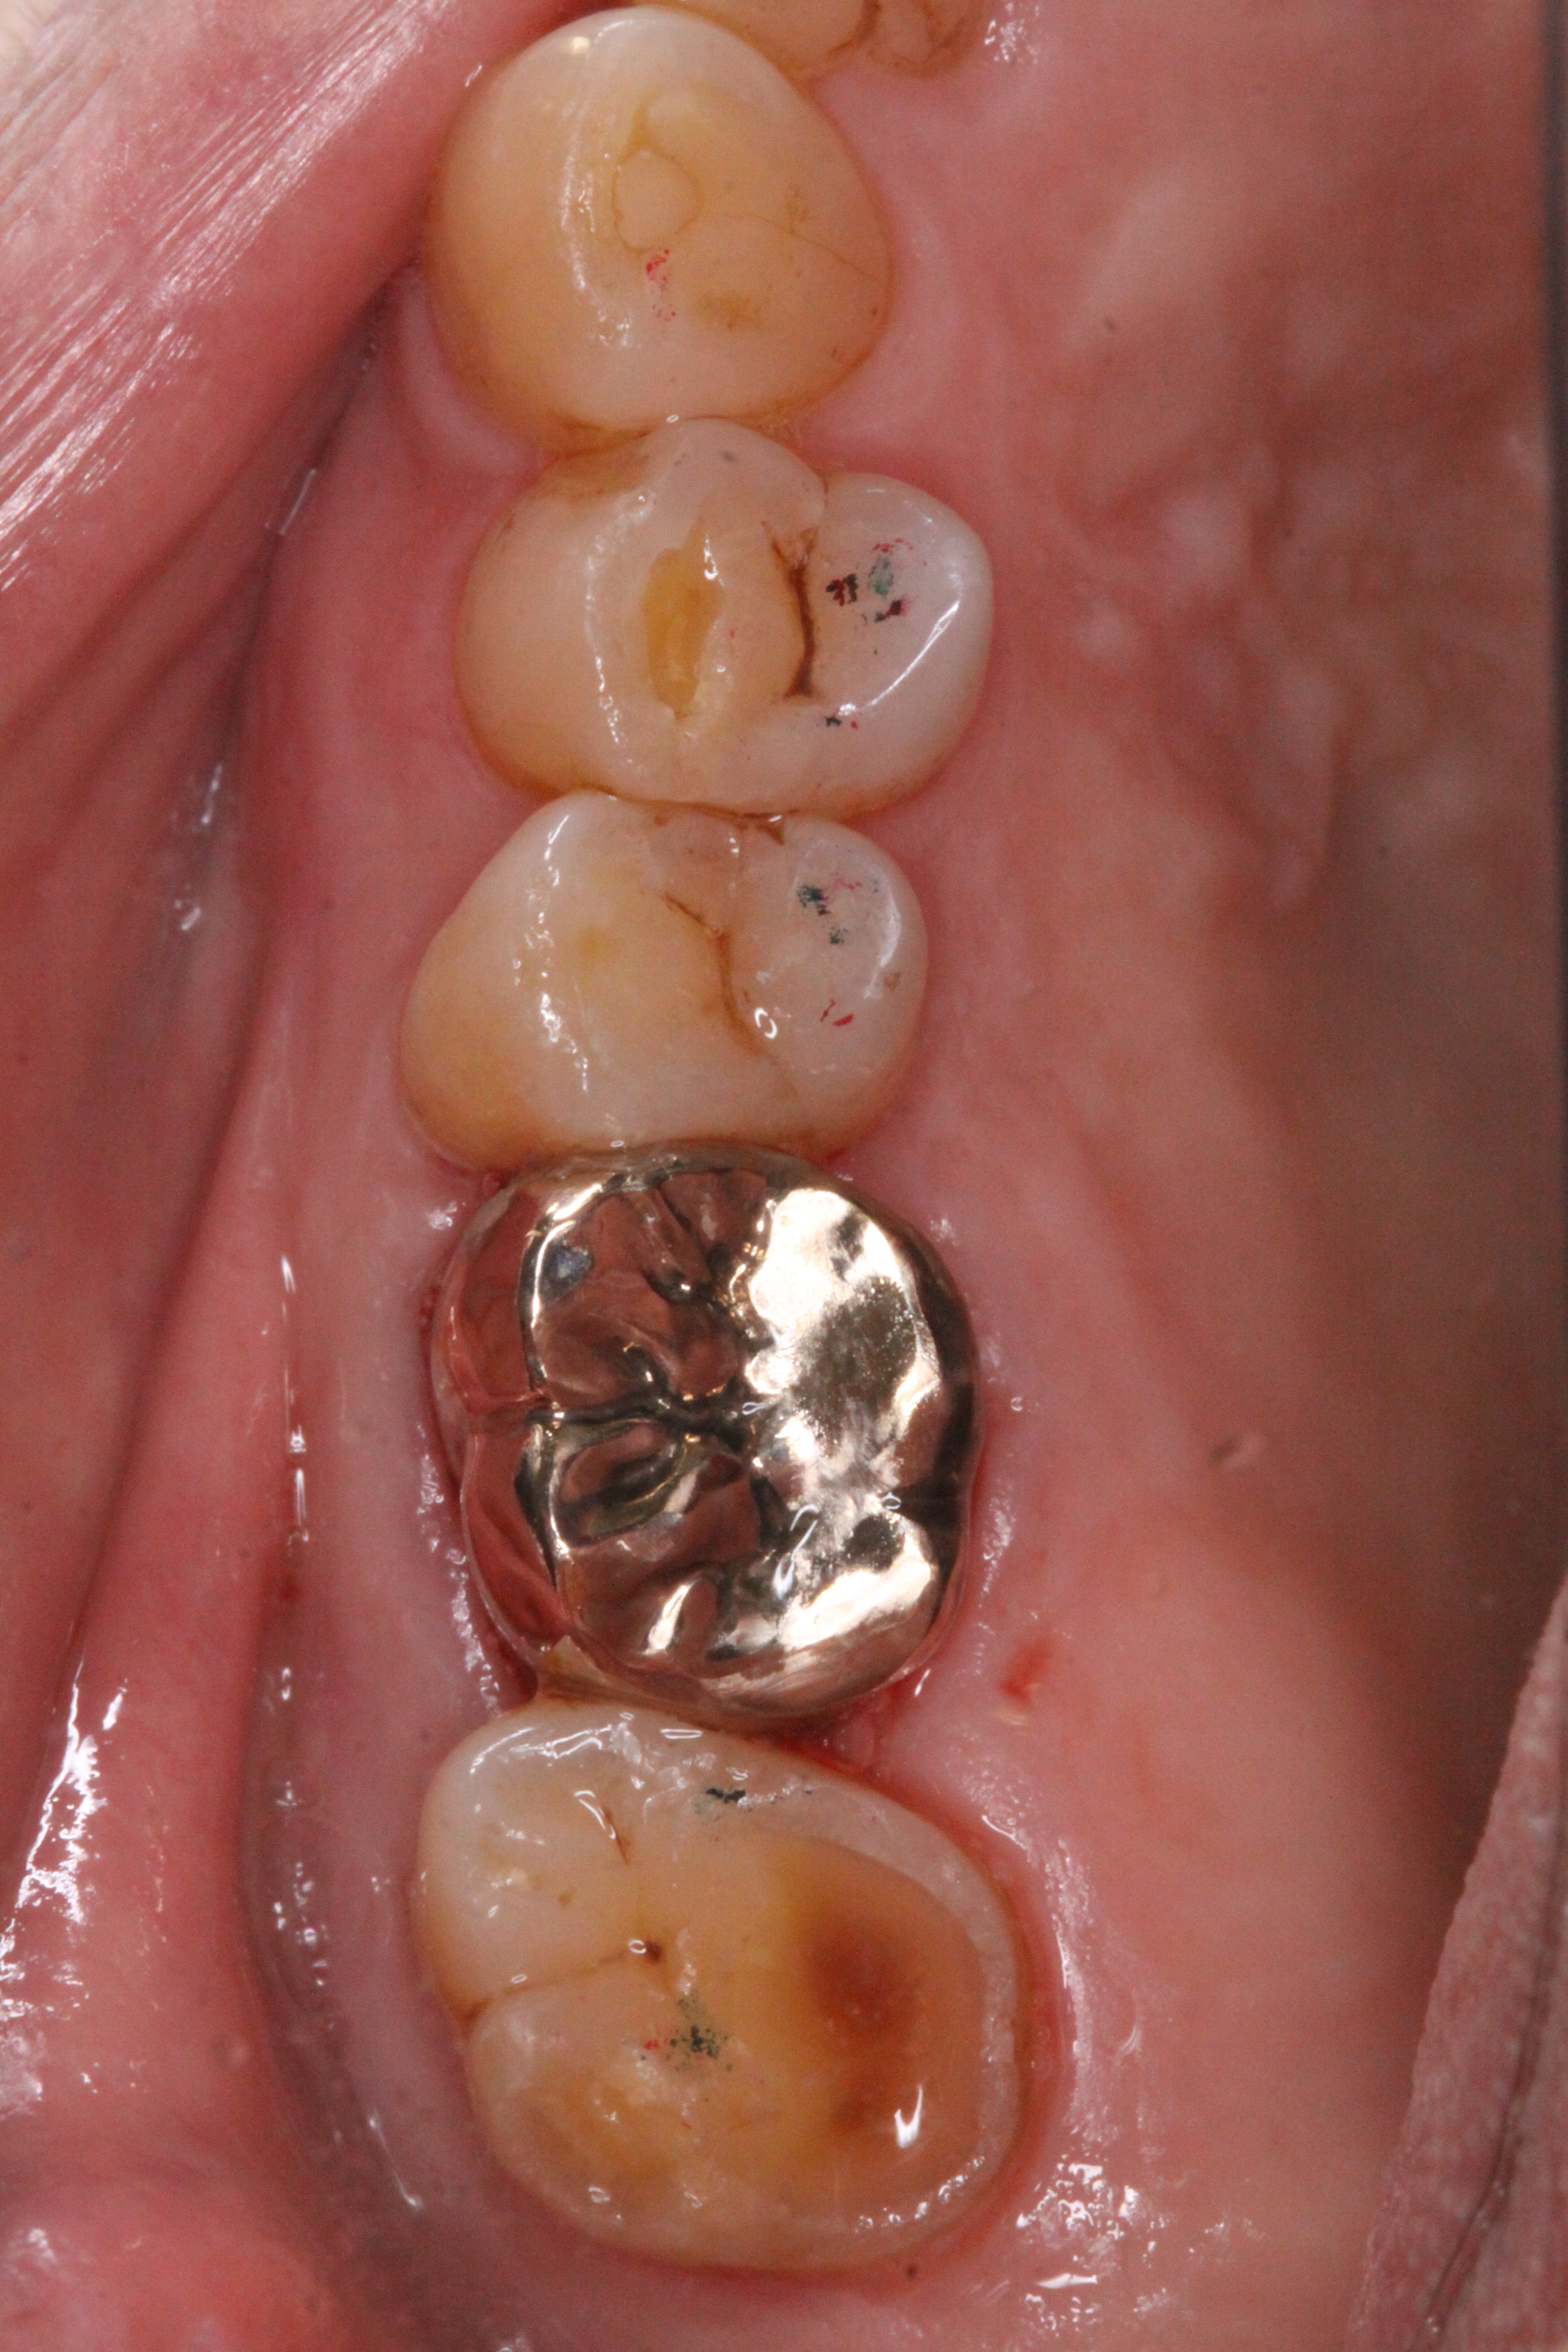

補綴後

数カ月経過観察後、状態も良くなってきたところで被せ物を入れました。